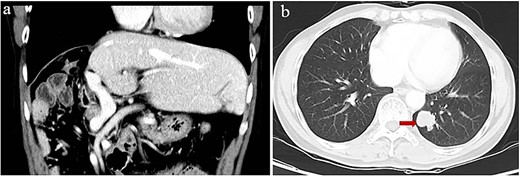

Our patient showed a recurrence-free survival time of 24 months after the first surgery (Fig. 4), slightly longer than the 20.3 months reported for patients receiving adjuvant hepatic artery infusion chemotherapy with 5-fluorouracil and oxaliplatin [36]. Our patient may also achieve recurrence-free survival of 24 months after repeat surgery: after nearly 24 months on adjuvant tislelizumab, no lesions were found on imaging even though the level of alpha-fetoprotein in serum remained slightly elevated. Such recurrence-free survive would be similar to the 25.2 months reported for patients at our medical center who received adjuvant ICIs with or without tyrosine kinase inhibitors after curative surgery [6].

Concentration of alpha-fetoprotein in the patient’s serum over the course of clinical interventions. BCLC, Barcelona Clinic Liver Cancer; PET-CT, positron-emission tomography/computed tomography; RECIST, Response Evaluation Criteria in Solid Tumors; SBRT, stereotactic body radiation therapy.

The alpha-fetoprotein level in our patient’s serum began to rise rapidly after 8 months of adjuvant ICI treatment; after 16 months of treatment, lung metastasis was detected. Our experience highlights the usefulness of elevated alpha-fetoprotein as a marker of tumor recurrence, metastasis, or de novo growth [11]. Moreover, this case report highlights the need for non-inferiority clinical trials to explore shorter adjuvant ICI therapy to maximize benefit while minimizing risks. Lastly, our case justifies further studies into the effects of adjuvant ICIs on recurrence in HCC patients after curative treatment.